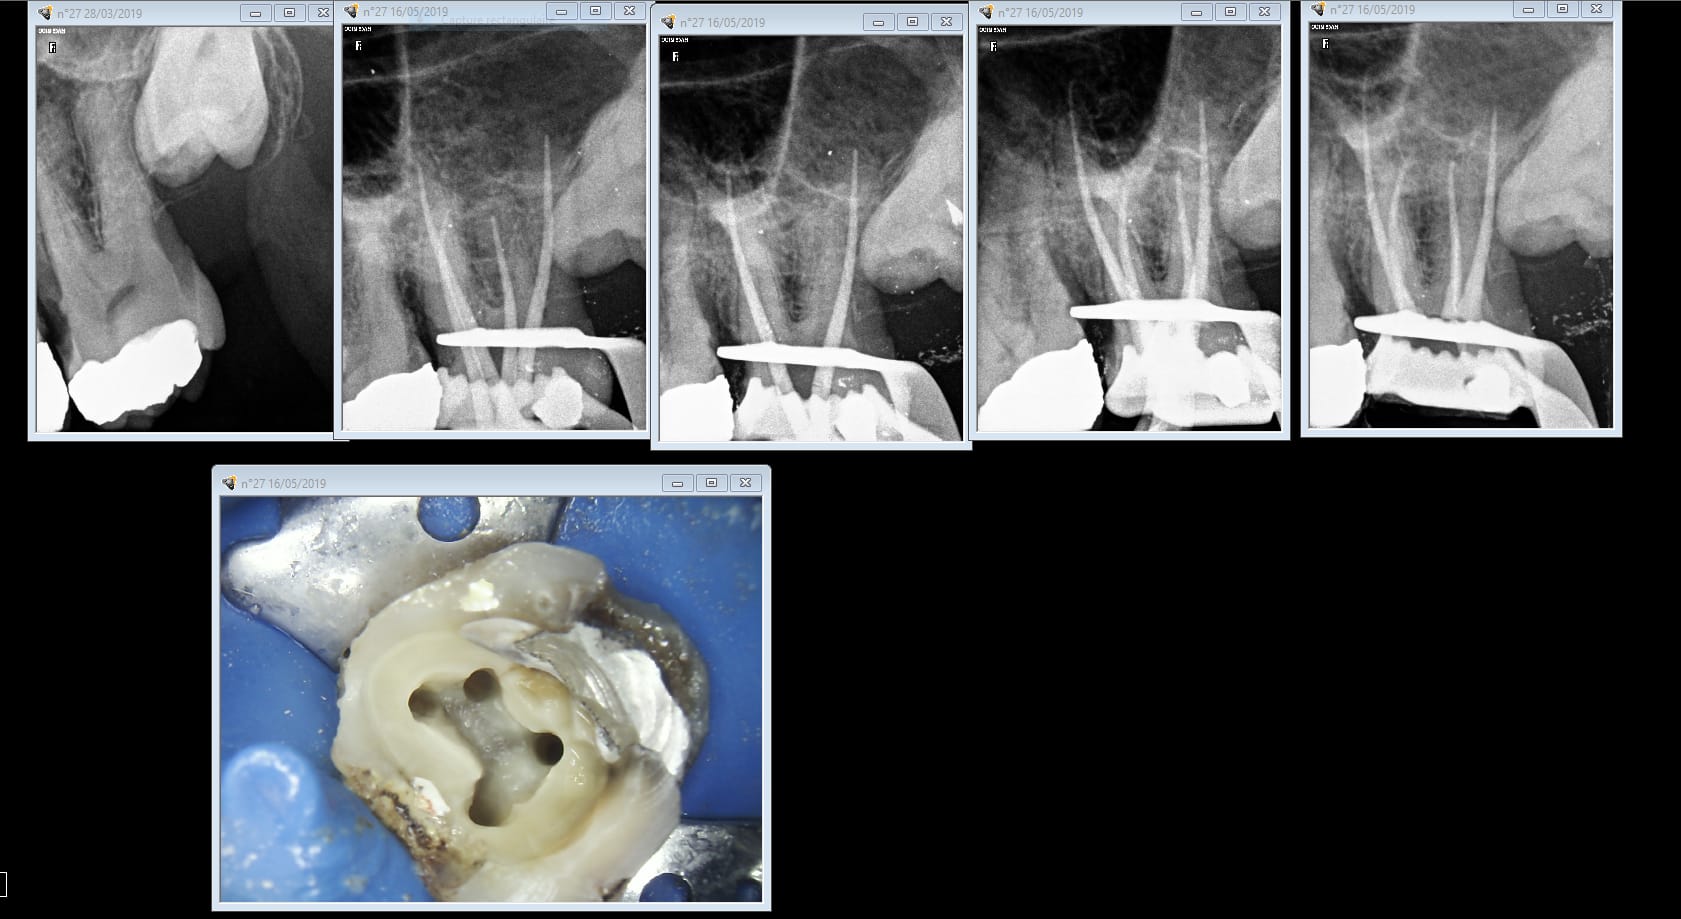

J'aimais bien quand Chicot postait ses endos.

Ah c'est toi qui l'a récupéré!-)

Pour personnellement en avoir fait les frais je peux te dire que les radios cones coupés ont un intérêt. Tu peux m'expliquer comment le cone de gutta en palatin a disparu ? Je coupe les 3 cones en meme temps et je ne m'aperçois pas qu'il y en a un qui s'est barré. Je ne pense pas que ça soit volontaire entre confrères ça ne se fait pas. Non ? -)))